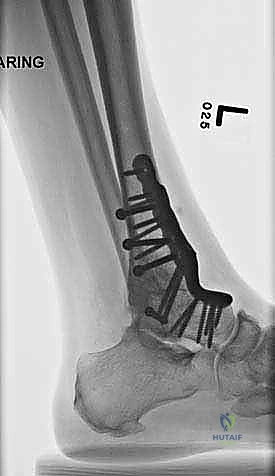

- الأشعة السينية أثناء الوقوف (Weight-bearing X-rays): هي الفحص الذهبي والأهم. يجب أن تؤخذ الأشعة والمريض واقف لتحمل الوزن. تظهر الأشعة تضيق المسافة المفصلية (دليل على فقدان الغضروف)، وجود نتوءات عظمية، تصلب العظم، وأي انحراف في محور المفصل.

| طرق العلاج | أدوية مضادة للالتهابات (NSAIDs)، أحذية طبية مخصصة (Rocker-bottom shoes)، دعامات الكاحل (AFO)، حقن الكورتيزون أو البلازما (PRP)، العلاج الطبيعي. | جراحة إزالة الغضاريف التالفة ودمج العظام (Arthrodesis) باستخدام مسامير وألواح معدنية. |

- تثبيت ميكانيكي حيوي أقوى: يتيح المدخل الأمامي وضع شريحة معدنية (Anterior Plate) على الجانب الأمامي للمفصل. من الناحية الميكانيكية الحيوية (Biomechanics)، يعتبر الجانب الأمامي هو "جانب الشد" (Tension side) أثناء المشي. وضع الشريحة هنا يوفر تثبيتاً فائق القوة ويقلل من معدلات عدم الالتئام.

- التخطيط الجراحي الرقمي: باستخدام صور الأشعة المقطعية، يقوم الدكتور هطيف بتخطيط الجراحة على الكمبيوتر لاختيار حجم المسامير والشرائح المناسبة بدقة مليمترية.